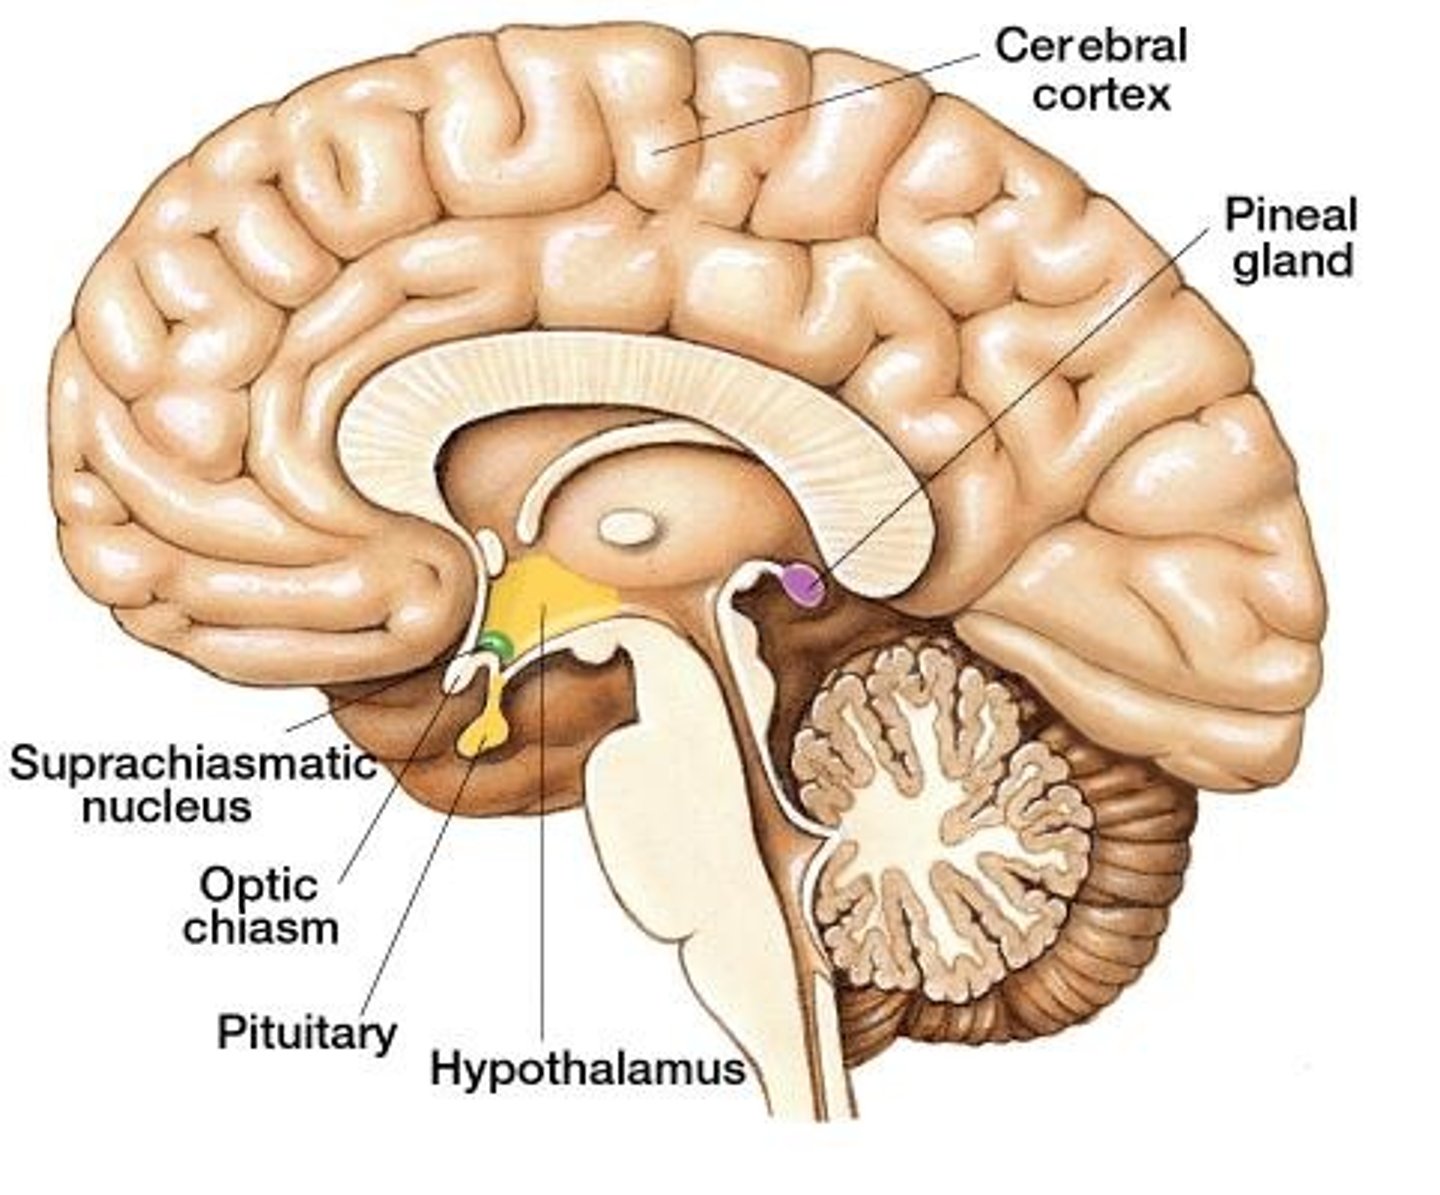

hypothalumus

small area near the base of the brain that is above the pituitary gland

pituitary gland

gland at the base of the brain that dangles under the hypothalamus

Pineal Gland

small pea sized gland that can be found posterior to the thalamus

hypothalamus hormones

ADH, oxytocin, regulatory hormones

pituitary gland hormones

LH, FSH, GH, TSH, ACTH, Prolactin, Oxytocin, ADH

pineal gland hormone

melatonin